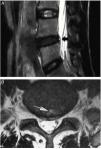

The study of degenerative pathology of the intervertebral disc (IVD) with magnetic resonance imaging (MRI) has generated such an extensive and ambiguous terminology that it causes confusion. The loss of the nucleus pulposus signal intensity (ISNP) in the T2 sequence of MRI, secondary to the early decrease in water content, is generally described as «black disc», a term spread as a synonym for degenerative disc disease. On the other hand, to designate a supposedly symptomatic dehydrated disc, the following names have been introduced: «painful black disc», «black disc syndrome» and «black disc disease». In this way, the physiological dehydration of the NP present in the entire population from the third decade on, is arbitrarily considered a presumed radiological marker of discogenic back pain, with the consequent risk of being the target of unnecessary interventions. Dehydrated discs suspected of being a source of pain present, in addition to the decrease in ISNP, other radiological signs such as a high intensity zone (HIZ) in the posterior part of the annulus fibrosus (AF), protrusion, loss of height or Modic changes.